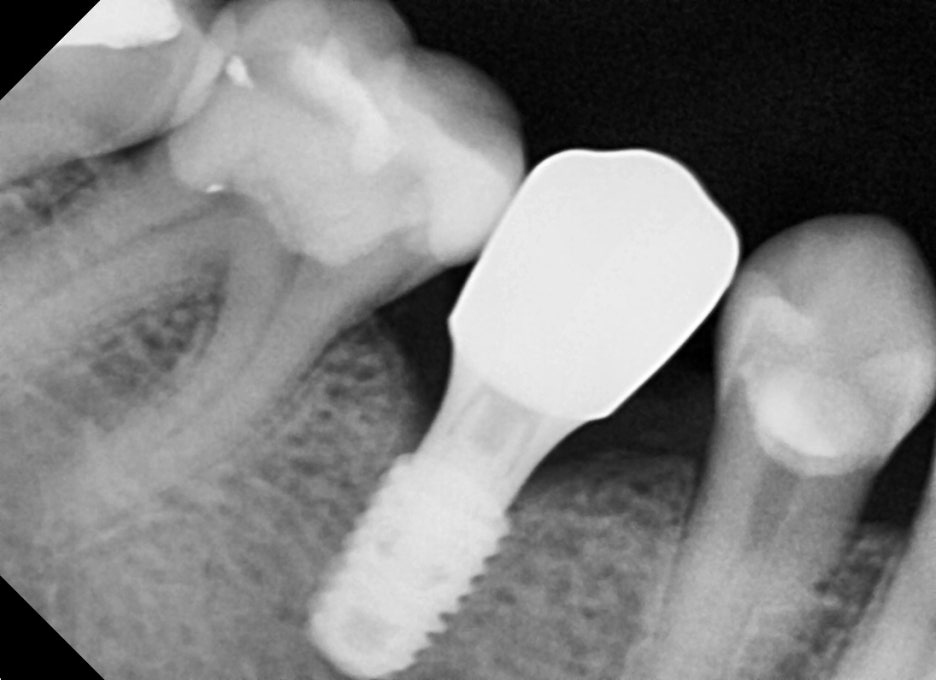

Panoramic imaging showed that the lower right molar had fractured

and could not be preserved.

It was diagnosed as a case in which immediate implant placement after extraction was possible.

The upper right premolar had been missing for a long time,

but because the degree of bone resorption in the jawbone was not severe,

implant treatment was possible without additional bone grafting.

1st visit: #45 extraction + immediate implant,

#15 implant placed simultaneously